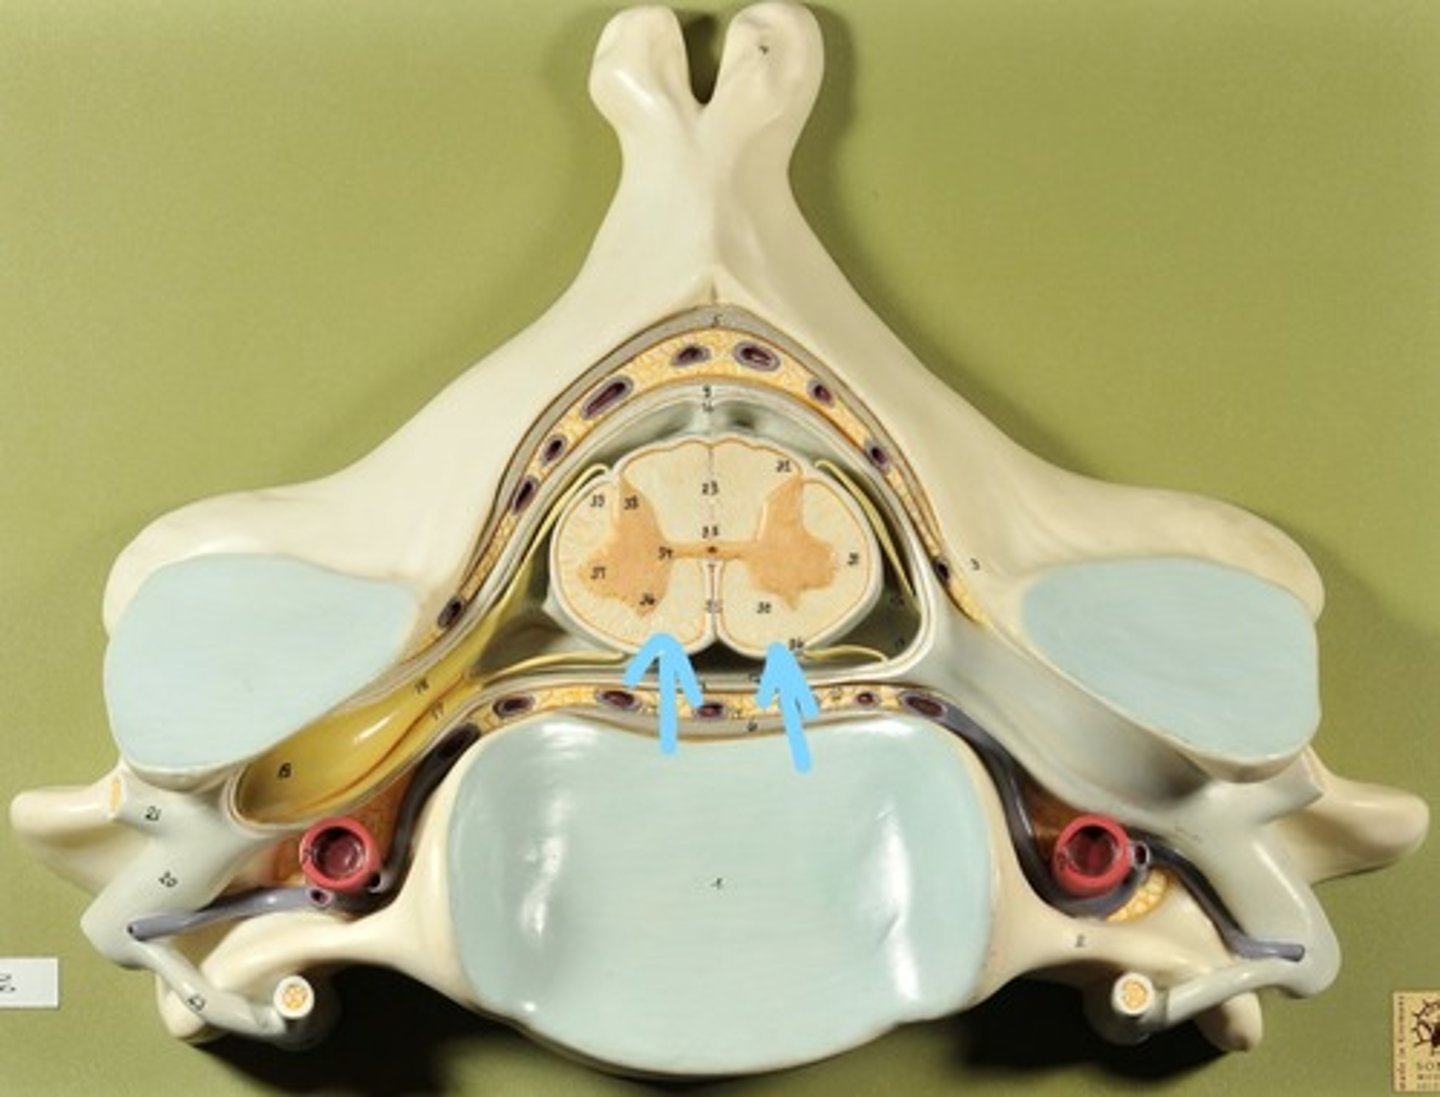

Identify all structures of spinal cord

White Matter of spinal cord

gray matter of spinal cord

Ventral Horns (gray matter)

Lateral Horns (gray matter)

Dorsal horns (gray matter)

Anterior Columns (white matter)

Lateral Columns (white matter)

Posterior Column (white matter)

central canal of spinal cord

Identify all structures

Pia Mater

Subarachnoid Space

Arachnoid mater

Subdural Space (brown line)

Dura mater

Epidural Space

Dorsal Root Ganglion

Dorsal Root

Ventral Root

Spinal Nerve